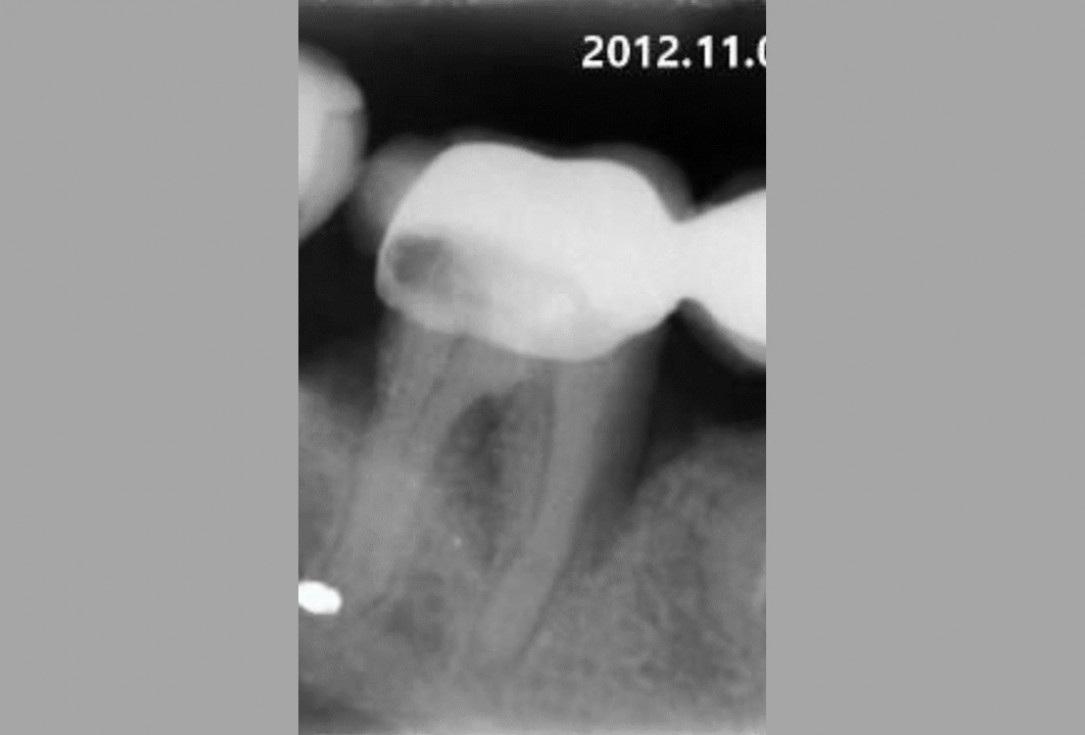

01/06 - Pre-operative radiographic view.Intrabony defect treated using Straumann® Emdogain®, cerabone® and Jason® membrane - Dr. D. B. Hangyási